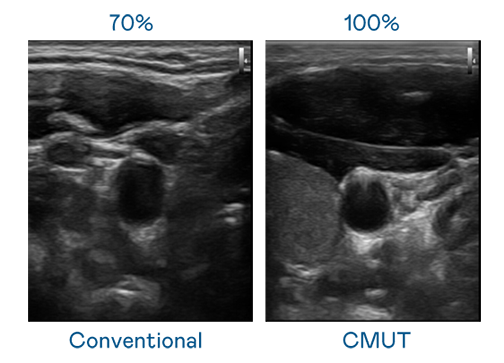

CMUT 技術是一種用電容式微機電元件來產生超音波訊號的技術。與傳統 PZT 壓電式技術相比,CMUT 頻寬增加 30%,更寬頻的超音波訊號讓影像解析度大幅提升,是實現高影像品質醫療超音波掃描、促進精準醫療發展的關鍵技術。

大頻寬帶來超清晰影像

超音波影像的解析度高低,首先取決於探頭能發出的訊號頻寬。j9九游会(中国)官方网站 CMUT 可提供高清晰的超音波訊號,提供高頻寬、高靈敏度、影像紋理細節更高的超音波影像,協助醫護人員縮短影像判讀時間及利用精準的醫療影像進行診斷。